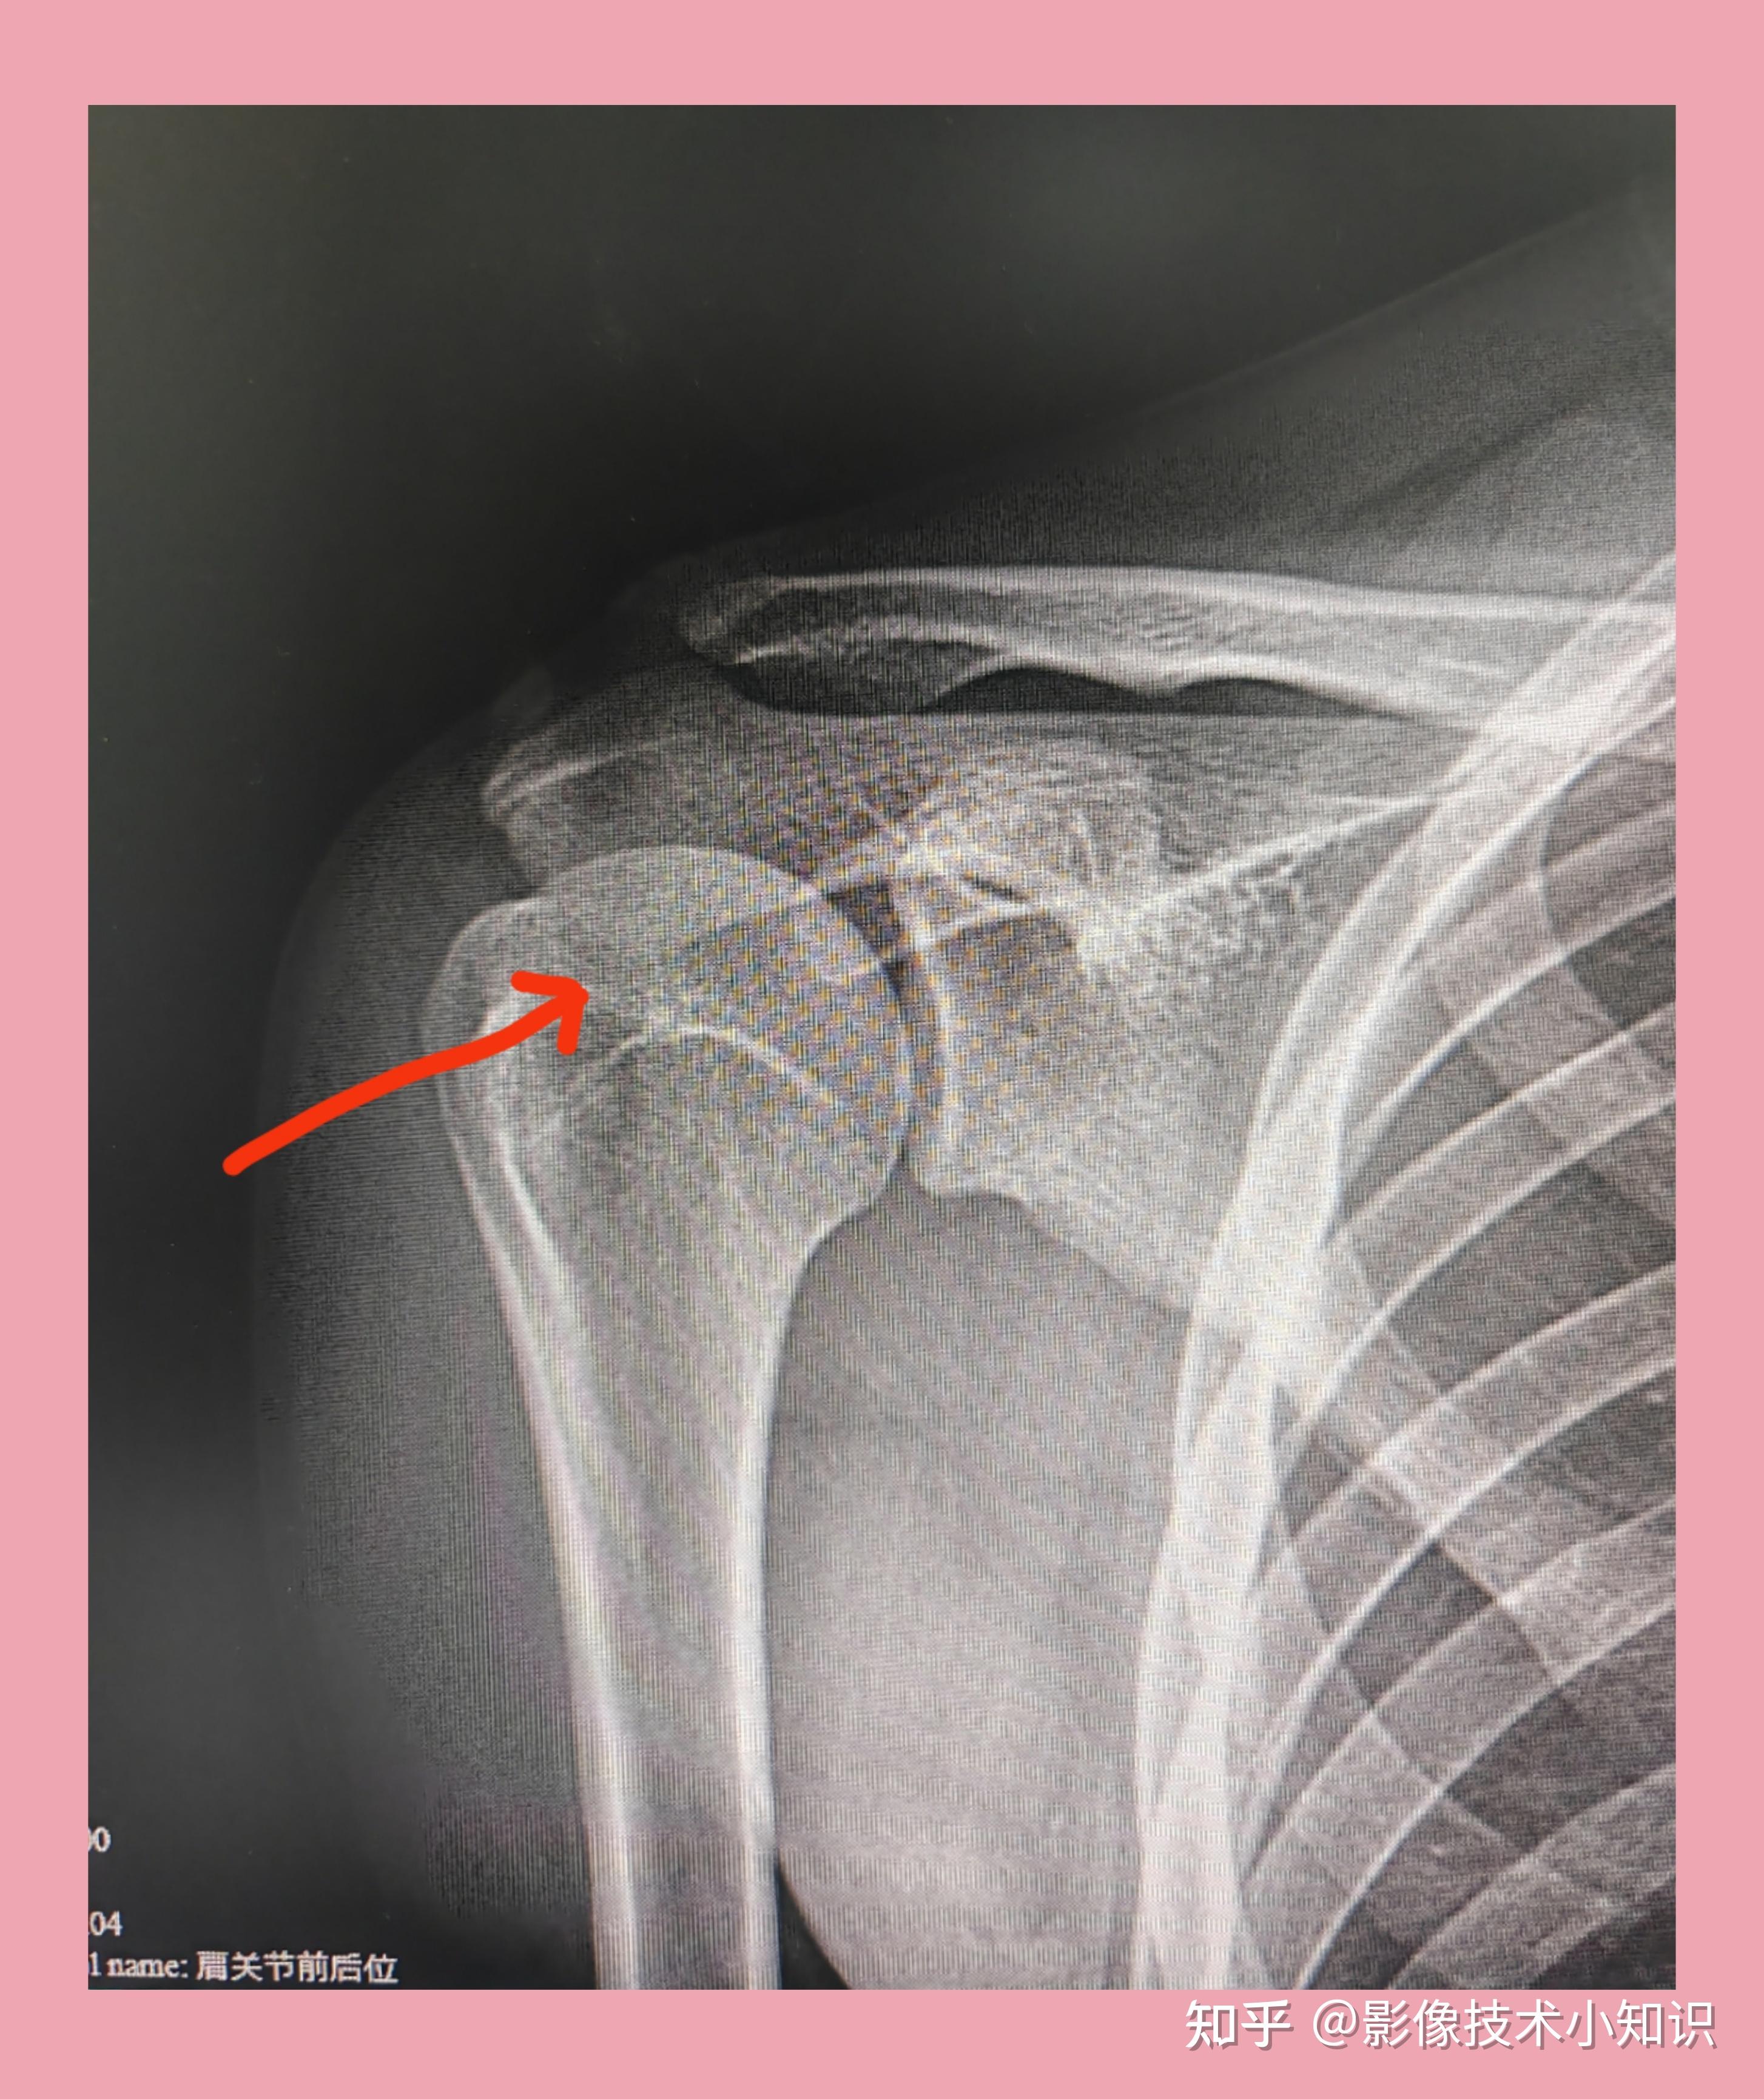

摔伤以后肩关节不能上举,活动还伴有弹响,是骨折了吗?

图片尺寸1220x1126